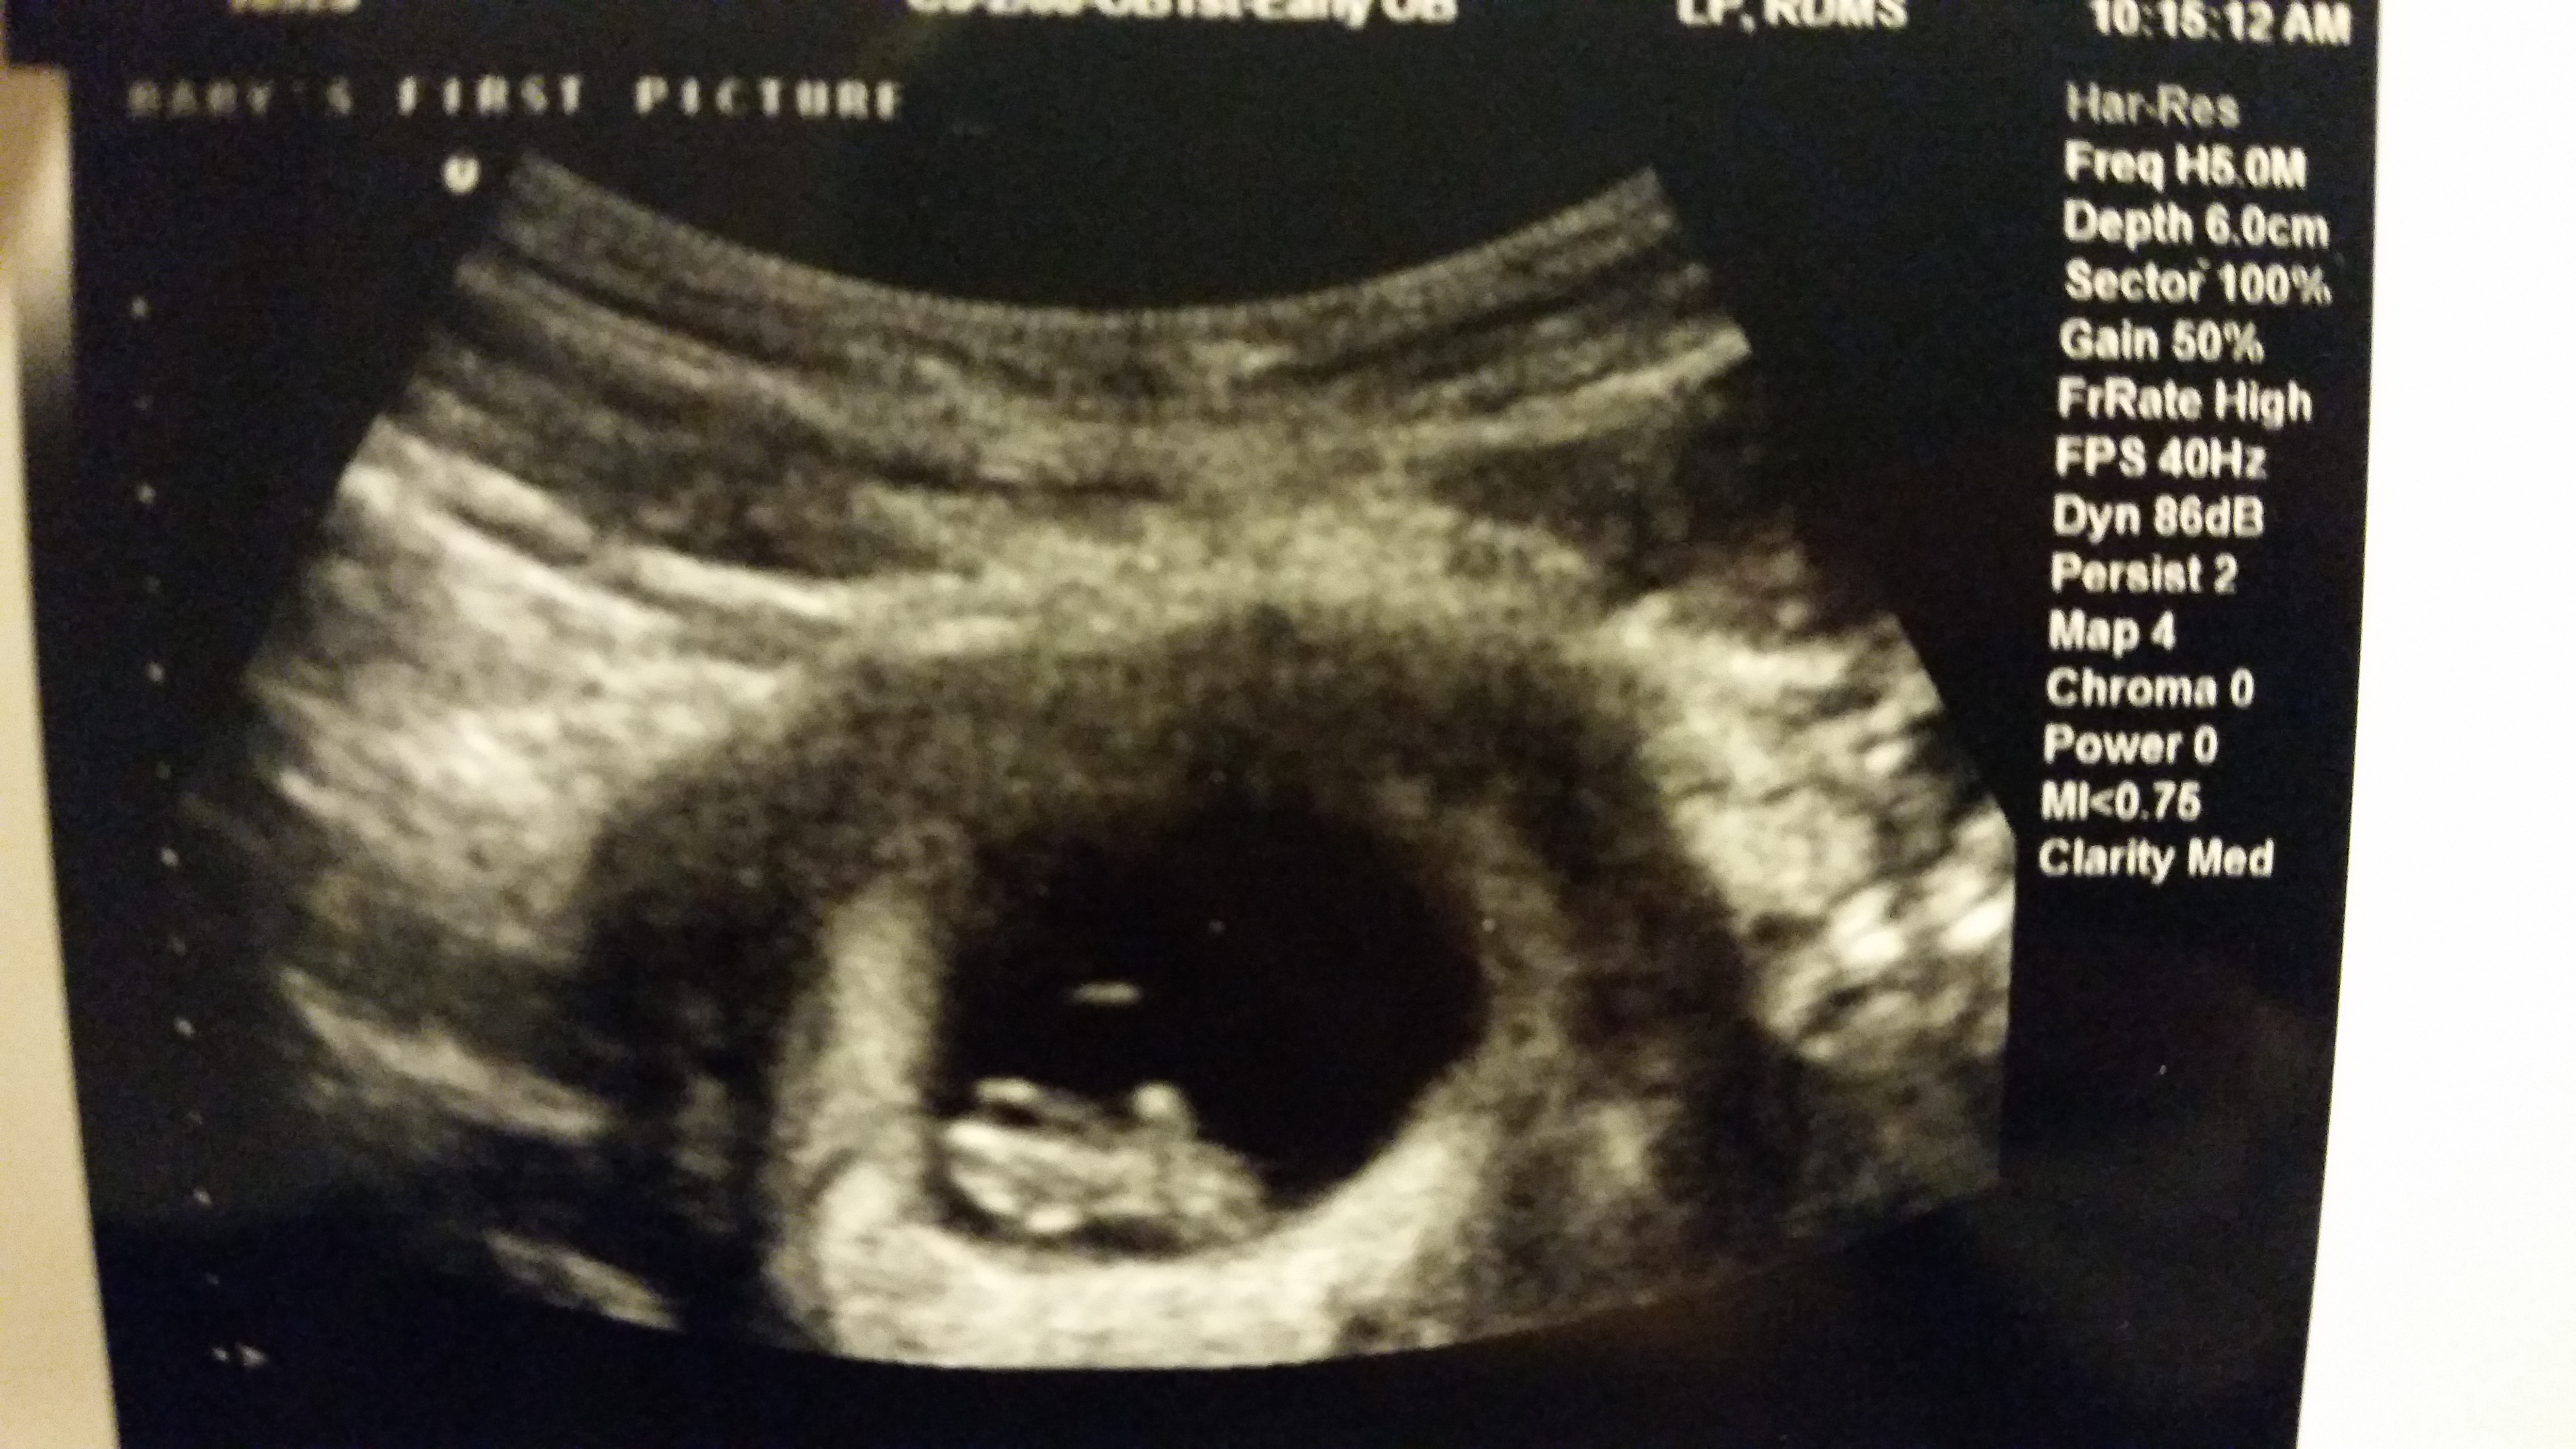

• Our little tadpole!! ❤️ 8weeks 2days!!! External US done at the ER after some bleeding!! HR 144bpm we were so relieved and excited to see that little blip!!!! Best feeling ever after having a bleeding scare!!!!